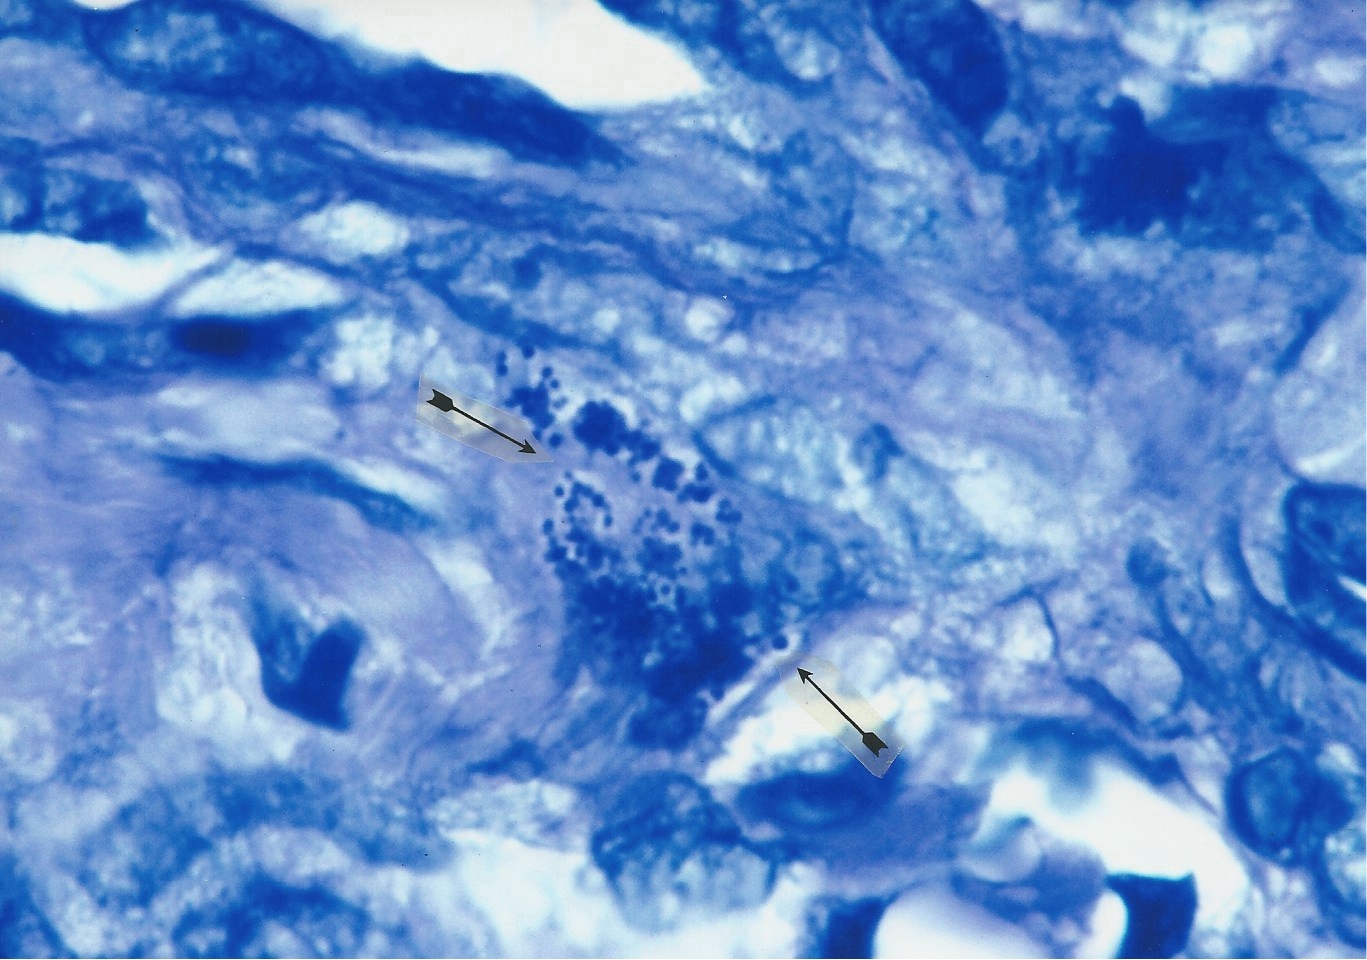

Figures 4 and 5 show African eosinophilic bodies in AIDS-related Kaposi’s sarcoma of the skin.

Figure 4. AIDS-related Kaposi’s sarcoma of the skin. Arrows point to a collection of tightly-packed, variable sized, transparent,

balloon forms of African eosinophilic bodies in the dermis. Hematoxylin-eosin stain, x1000.

Figure 5. AIDS-related Kaposi’s sarcoma of the skin. In center a nest of pink-stained coccoid forms wedged between

the collagen fibers of the dermis, and consistent with small forms of eosinophilic bodies.